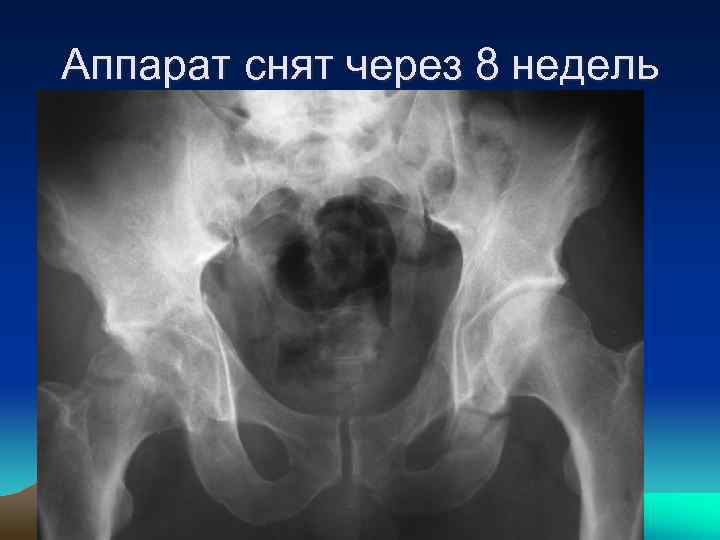

• закрытая репозиция правой вертлужной впадины в аппарате внешней фиксации с помощью трансартикулярно проведенного стержня

Аппарат снят через 8 недель

Результат через 1 год